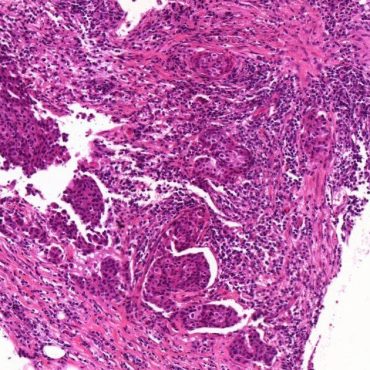

TRAIN YOURSELF